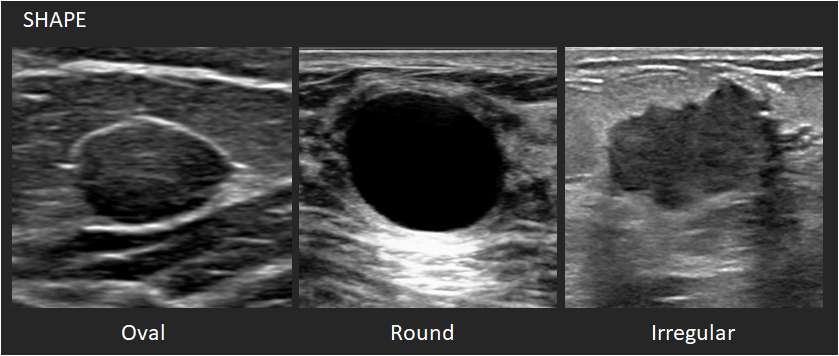

Shape:

- Oval: This shape is elliptical or egg-shaped. An oval mass may include two or three undulations.

- Round: This shape is spherical, ball-shaped, circular or globular.

- Irregular: This shape is neither round nor oval.